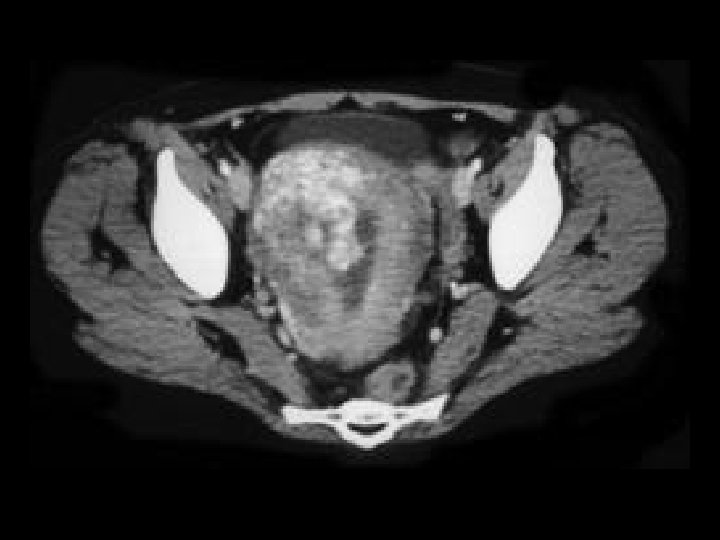

Bladder TCC • Findings: – Diffuse wall thickening of the bladder • ddx: – Underdistension – Muscular hypertrophy from outlet obstruction – Cystitis